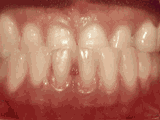

Overbite: Protruding front teeth

overbite

At age ten, patient had a big overbite with the top teeth protruding beyond the bottom. She had two phases of treatment. The first helped her jaws to grow more harmoniously; the second aligned her teeth and bite. At age thirteen, she was proudly displaying her new smile.